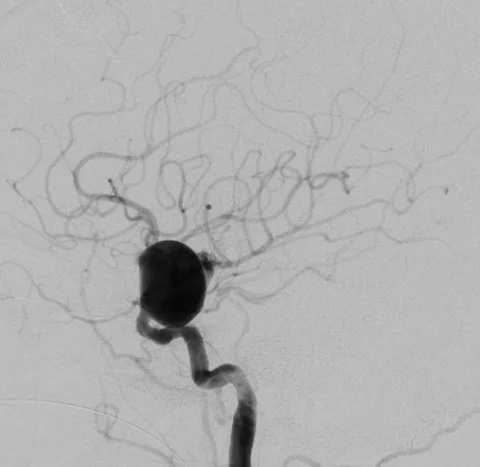

icapipepreap.jpg